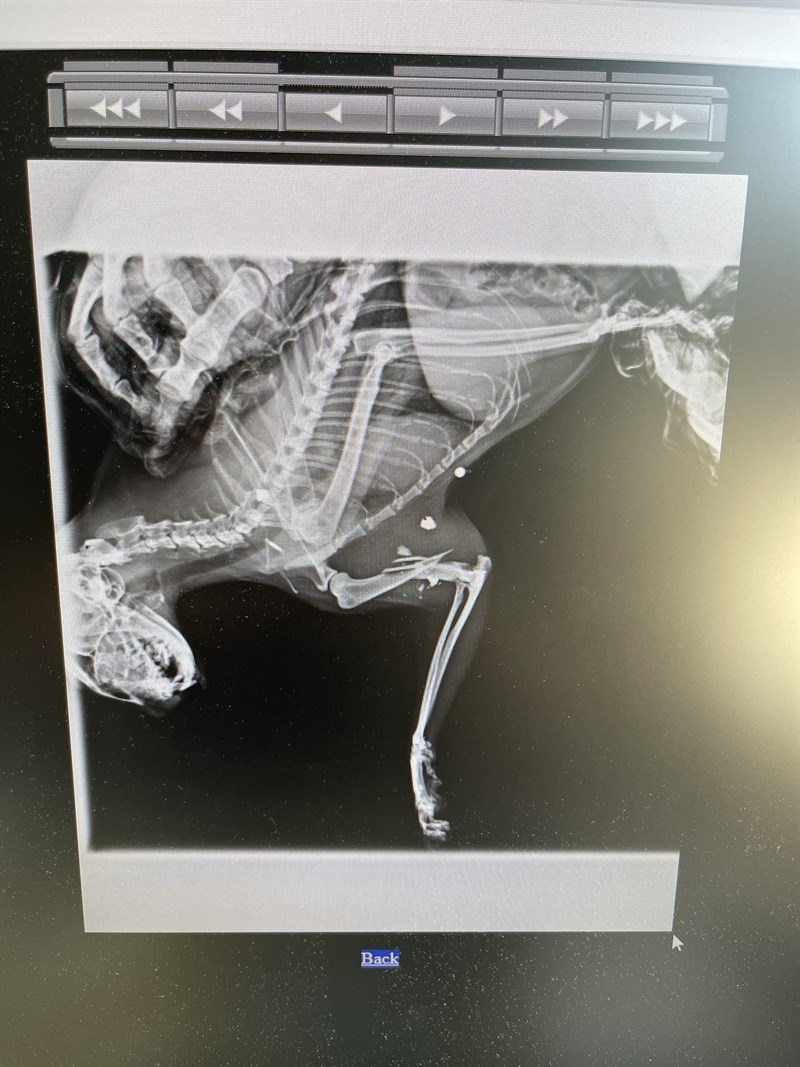

È successo a maggio: hanno sparato a un gatto che da anni vive nella colonia felina della stazione di S. Piero a Sieve. Il gatto si stava allontanando leggermente dalla colonia quando è stato colpito da più pallini, uno dei quali ha fratturato l'osso della sua zampa anteriore, creando una frattura interna.

Successivamente, la ASL ha contattato l'ambulatorio veterinario in cui il gatto era stato già trasferito, comunicando che non avrebbero coperto le spese per le cure, e che spettavano al Comune. Il Comune, a sua volta, ha risposto che non era di sua competenza intervenire e che non disponeva dei fondi necessari. Nonostante ciò, grazie alla tenacia della referente e delle volontarie, il gatto è stato operato con successo nella clinica veterinaria e, grazie alla collaborazione del titolare dell'ambulatorio, che ha interagito con l'ASL, le spese saranno sostenute dall'azienda stessa.